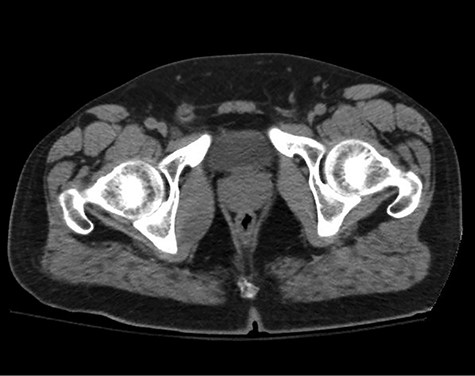

A healthy 47-year-old male with past medical history significant only for hypertension and nephrolithiasis presented to Englewood Health Medical Center in October 2019 with right flank pain radiating to the pubis, hematuria, hard stool with straining and fifteen pound weight loss over 6 months. On physical examination, multiple café au lait spots, small neurofibromas on his trunk and arms and axillary and inguinal freckling were observed. On CT scan, he was found to have a 10.1-cm soft tissue mass in the right hemipelvis and a nephroureteral stent with a 3-mm stone in the proximal right ureter (Fig. 1). Further history revealed the patient had a known pelvic mass discovered on CT approximately 10 years prior (Fig. 2), which was again observed on CT in June 2019 during a hospitalization for nephrolithiasis at Hackensack University Medical Center (Fig. 3); he had been lost to follow-up.

HUMC CT 11/14/09: 3.3 × 6.6 × 3.0-cm-sized right pelvic wall soft tissue mass.